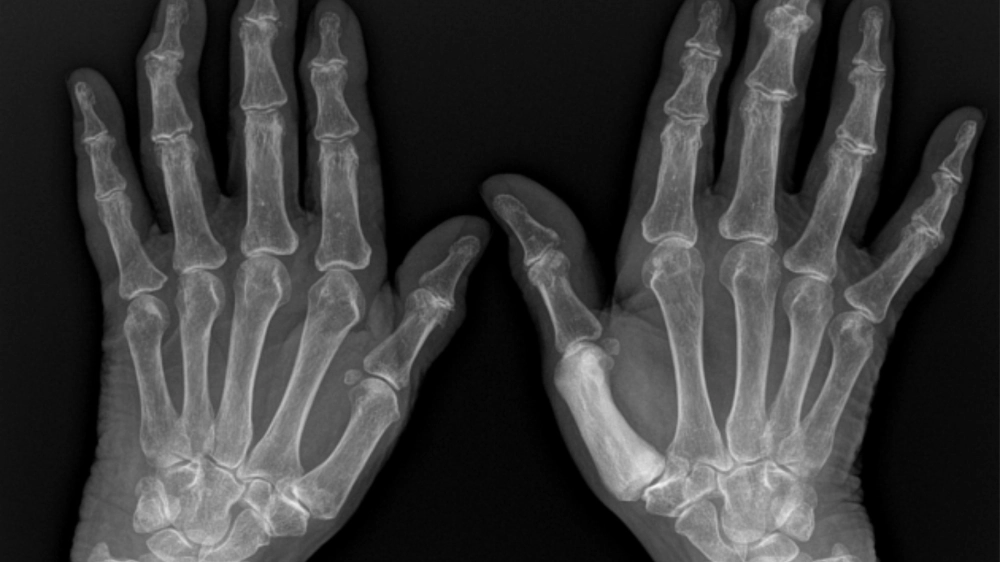

X-quang cho thấy sự biến dạng của bệnh Paget xương